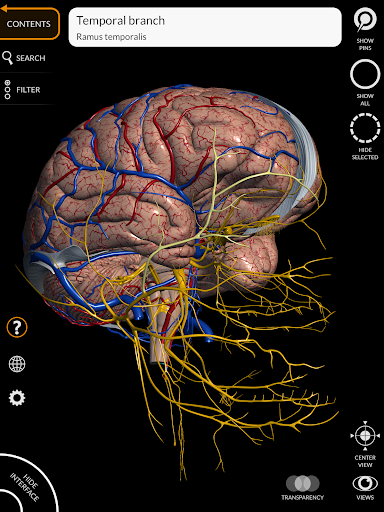

"Anatomy 3D Atlas" cho phép bạn nghiên cứu giải phẫu người theo cách dễ dàng và tương tác.

Thông qua giao diện đơn giản và trực quan, bạn có thể quan sát mọi cấu trúc giải phẫu từ mọi góc độ.

Các mô hình giải phẫu 3D đặc biệt chi tiết và có kết cấu lên đến độ phân giải 4k.

MÔ HÌNH GIẢI PHẪU 3D

• Hệ thống thần kinh